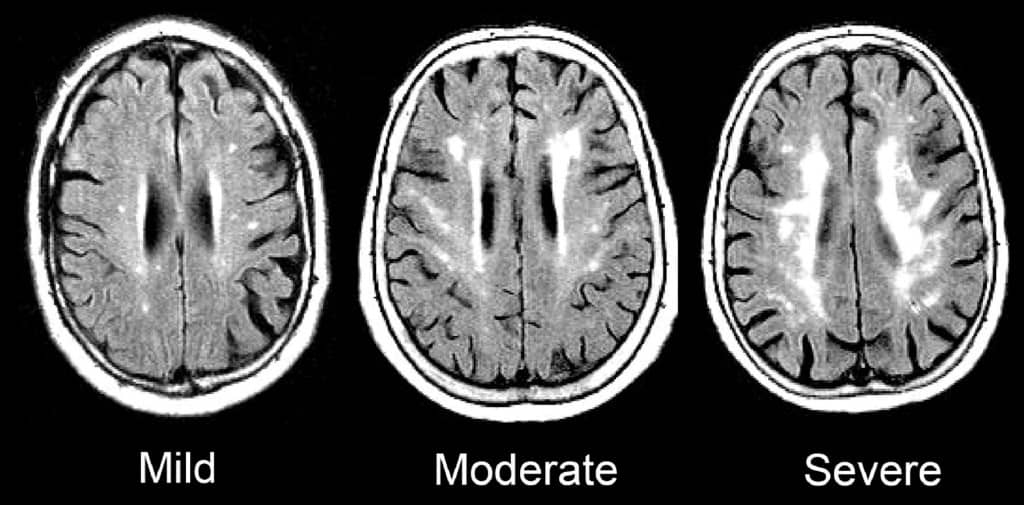

Such signs of SVD may be described as “mild”, “moderate,” or “severe/extensive,” depending on how widespread they are.

Here is an enlargement of a good image, from the BMJ article “Changes in white matter as determinant of global functional decline in older independent outpatients.”

The severity of symptoms tends to correspond to whether radiological imaging shows the white matter changes to be mild, moderate, or severe.

- Transition to disability or death. In a 2009 study of 639 non-disabled older persons (mean age 74), over a three-year follow-up period, 29.5% of participants with severe white matter changes and 15.1% of participants with moderate white matter changes developed disabilities or died. In comparison, only 10.5% of participants with mild white matter changes transitioned to disability or death over three years. The researchers concluded that severity of cerebral SVD is an important risk factor for overall decline in older adults.